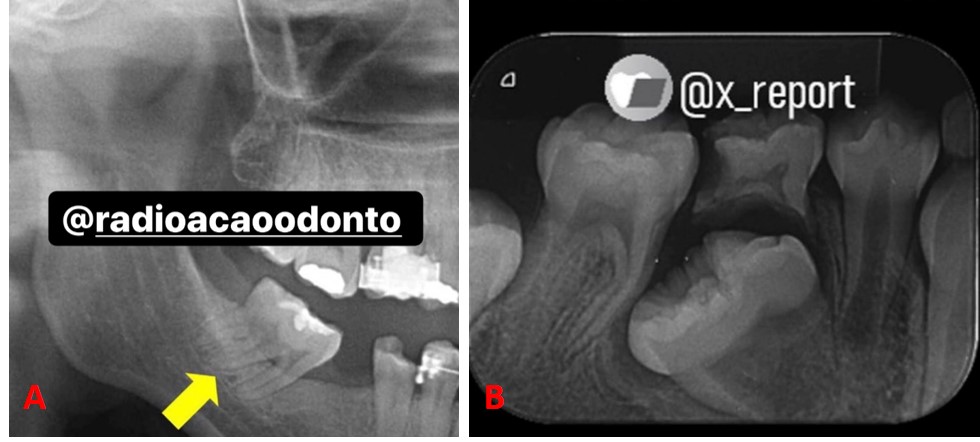

Na fusão dental, temos dentes que, em algum momento no período da sua formação (odontogênese), tentaram de fusionar. Por consequência disso, acontece a união de dois germes dentários adjacentes. Desse modo, encontram-se aderidos pela dentina, possuindo duas coroas e duas raízes. Um sinônimo para fusão é sinodontia.

Acredita-se que a fusão acontece quando dois germes dentários se formam tão próximos entre si que, conforme se desenvolvem, entram em contato e se fundem antes que ocorra a calcificação. Assim sendo, pode ser total ou parcial dependendo o estágio da odontogênese.

Essa condição é mais comum na dentição decídua e na região anterior. Importante observar que, nessa condição as coroas dos dentes fusionados normalmente parecem ser grandes e únicas podendo também ocorrer uma coroa bífida. Observem a Figura 1.

Assim, permitem a segurança ao orientar o profissional quanto ao tratamento específico do dente, juntamente com o exame clínico. Trago pra vocês um caso não tão comum de fusão de molares (Figura 3, A e B). Observem atentamente a imagem. Neste caso o diagnóstico diferencial da fusão incluem: geminação e macrodontia.